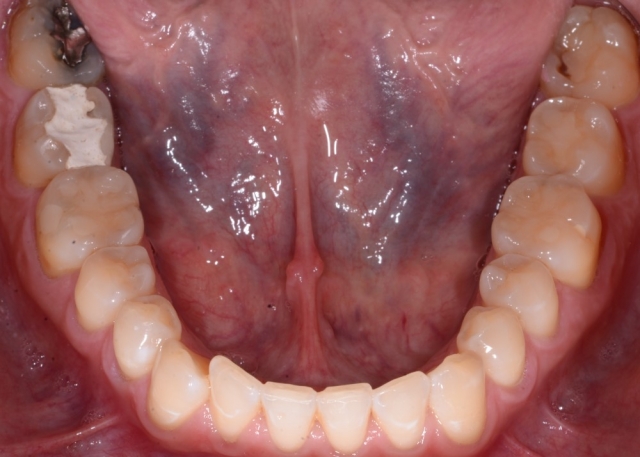

Recently in your practice, it’s very likely that you have: efficiently temporized a broken tooth and reassured a patient that it will be just fine; started endodontic therapy for a patient in acute pain and helped her sleep again; and placed composite on a chipped or broken front tooth and helped the patient smile again. (Figs. 1–3)